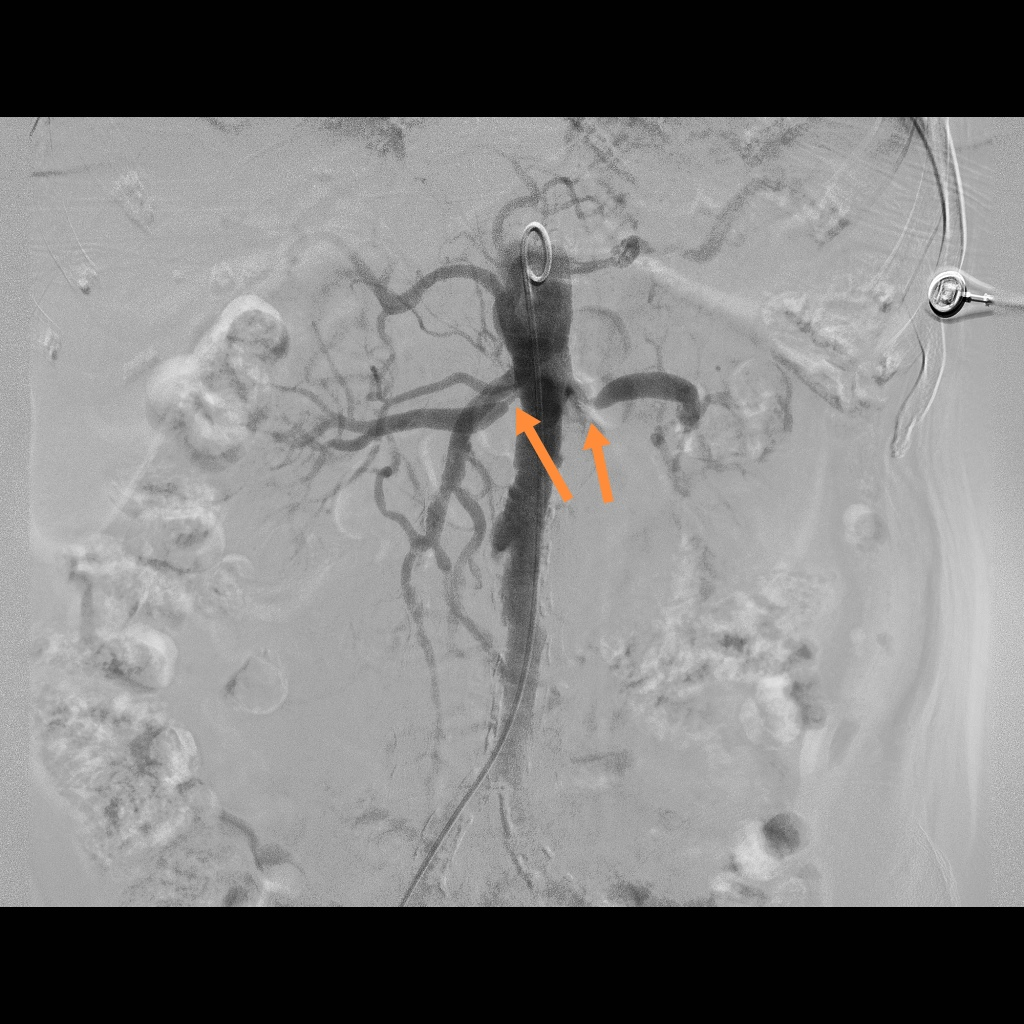

注:DSA下双侧肾动脉重度狭窄;